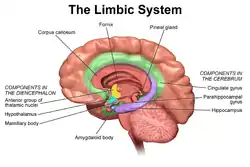

The limbic system, also known as the paleomammalian cortex, is a set of brain structures located on both sides of the thalamus, immediately beneath the medial temporal lobe of the cerebrum primarily in the forebrain.[1]

The limbic system is involved in lower order emotional processing of input from sensory systems and consists of the amygdala, mammillary bodies, stria medullaris, central gray and dorsal and ventral nuclei of Gudden.[3] This processed information is often relayed to a collection of structures from the telencephalon, diencephalon, and mesencephalon, including the prefrontal cortex, cingulate gyrus, limbic thalamus, hippocampus including the parahippocampal gyrus and subiculum, nucleus accumbens (limbic striatum), anterior hypothalamus, ventral tegmental area, midbrain raphe nuclei, habenular commissure, entorhinal cortex, and olfactory bulbs.[3][4][5]

Currently, it is not considered an isolated entity responsible for the neurological regulation of emotion, but rather one of the many parts of the brain that regulate visceral autonomic processes.[9] Therefore, the set of anatomical structures considered part of the limbic system is controversial. The following structures are, or have been considered, part of the limbic system:[10][11]

- Subcortical areas:

- Septal nuclei: a set of structures that lie in front of the lamina terminalis, considered a pleasure zone

- Hippocampus and associated structures: play a central role in the consolidation of new memories

- Amygdala: located deep within the temporal lobes and related with a number of emotional processes

- Nucleus accumbens: involved in reward, pleasure, and addiction

- Diencephalic structures:

- Hypothalamus: a center for the limbic system, connected with the frontal lobes, septal nuclei, and the brain stem reticular formation via the medial forebrain bundle, with the hippocampus via the fornix, and with the thalamus via the mammillothalamic fasciculus; regulates many autonomic processes

- Mammillary bodies: part of the hypothalamus that receives signals from the hippocampus via the fornix and projects them to the thalamus

- Anterior nuclei of thalamus: receive input from the mammillary bodies and involved in memory processing